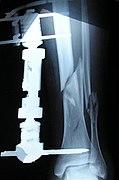

The following case study illustrates the Ilizarov apparatus treatment procedure for a fractured limb. The photographs are of the same patient during the course of treatment.

Front-left view of the Ilizarov apparatus treating a fractured tibia and fibula. The patient suffered an open fracture. It is located slightly above black metal ring. Photographs 1 through 4 are taken four weeks following the fracture and two weeks following the installation of the Ilizarov apparatus.